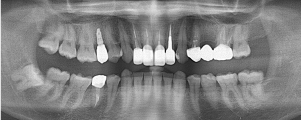

治療前のレントゲン

治療後のレントゲン

歯肉退縮により、以前他院で製作されたセラミック冠の審美障害があります。また時々、根元が腫れていたとのこと。前歯4本すべて根管治療を行い、ファイバーコアを入れてからオールセラミック(e-max)で修復しました。術後のレントゲンでは根尖性歯周炎が改善しています。